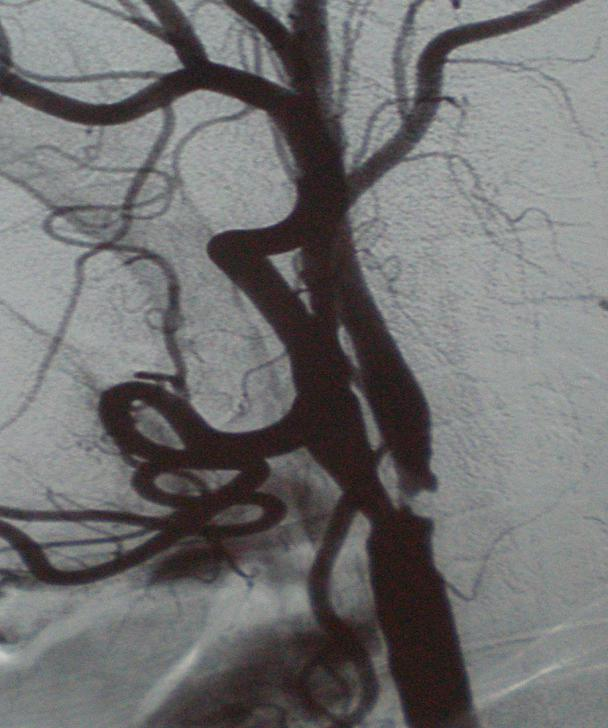

腦動(dòng)脈狹窄是指比原來(lái)的管腔變細(xì),是腦梗死的發(fā)病基礎(chǔ),容易造成偏癱、不能說(shuō)話、偏身麻木甚至昏迷致生命危險(xiǎn)。 腦動(dòng)脈狹窄到一定程度,除了藥物治療之外,是有支架植入辦法的,當(dāng)然頸動(dòng)脈狹窄也可以選擇頸動(dòng)脈內(nèi)膜剝脫術(shù)。原則上有臨床癥狀的腦動(dòng)脈狹窄50%、無(wú)癥狀的腦動(dòng)脈狹窄到70%有支架植入的指征。支架植入術(shù)是在狹窄部位植入支架,將狹窄部位打開(kāi)并維持已擴(kuò)張的管腔,就像一個(gè)即將堵塞的渠道被通開(kāi)了,預(yù)防再次腦缺血發(fā)生。以上兩幅圖片是頸動(dòng)脈支架植入前和支架植入后的圖片,希望給大家留下一個(gè)直觀印象。